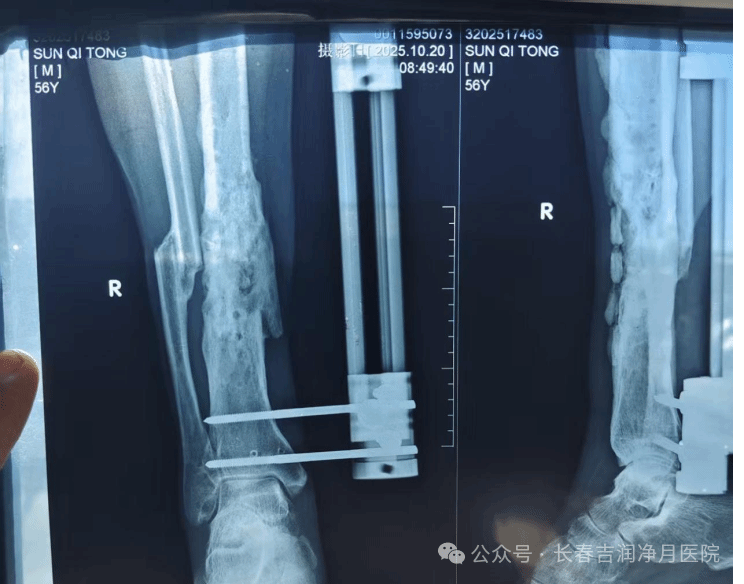

(于铁成主任团队第一次术后两次复查片)